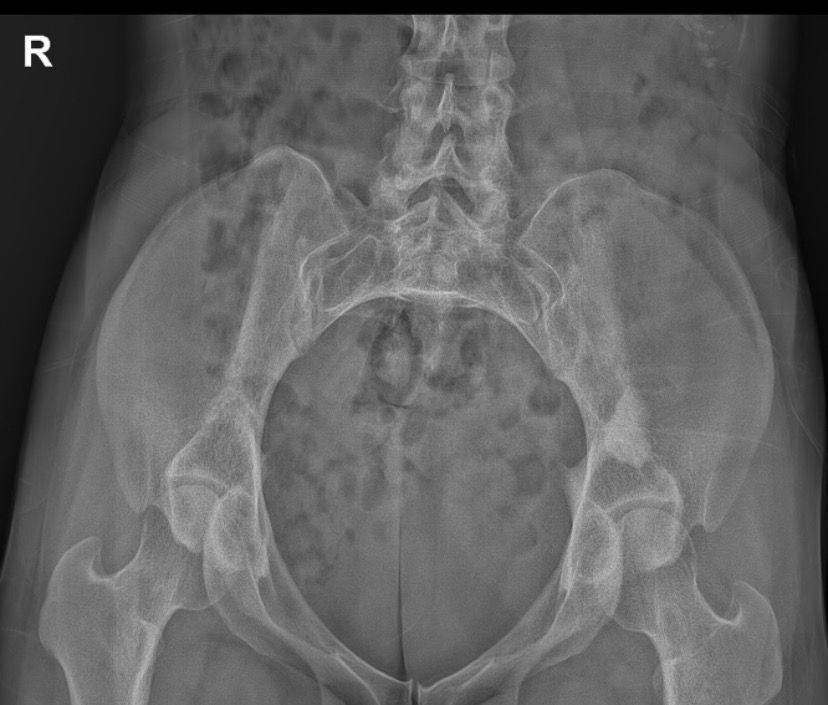

골반 x-Ray 사진 판독 좀 부탁드려요ㅜㅜ

엑스레이 찍자고 하셔서 찍었는데 왼쪽 골반뼈에 뭐가 보인다고 하시더라구요 혹인가… 하시면서 크게 신경 안쓰시는거처럼 말씀하셔서 그런가보다 하고 일단 물리치료 받고 오긴 했는데 시간이 갈수록 조금 걱정이 돼서요…

• 2번 째 사진